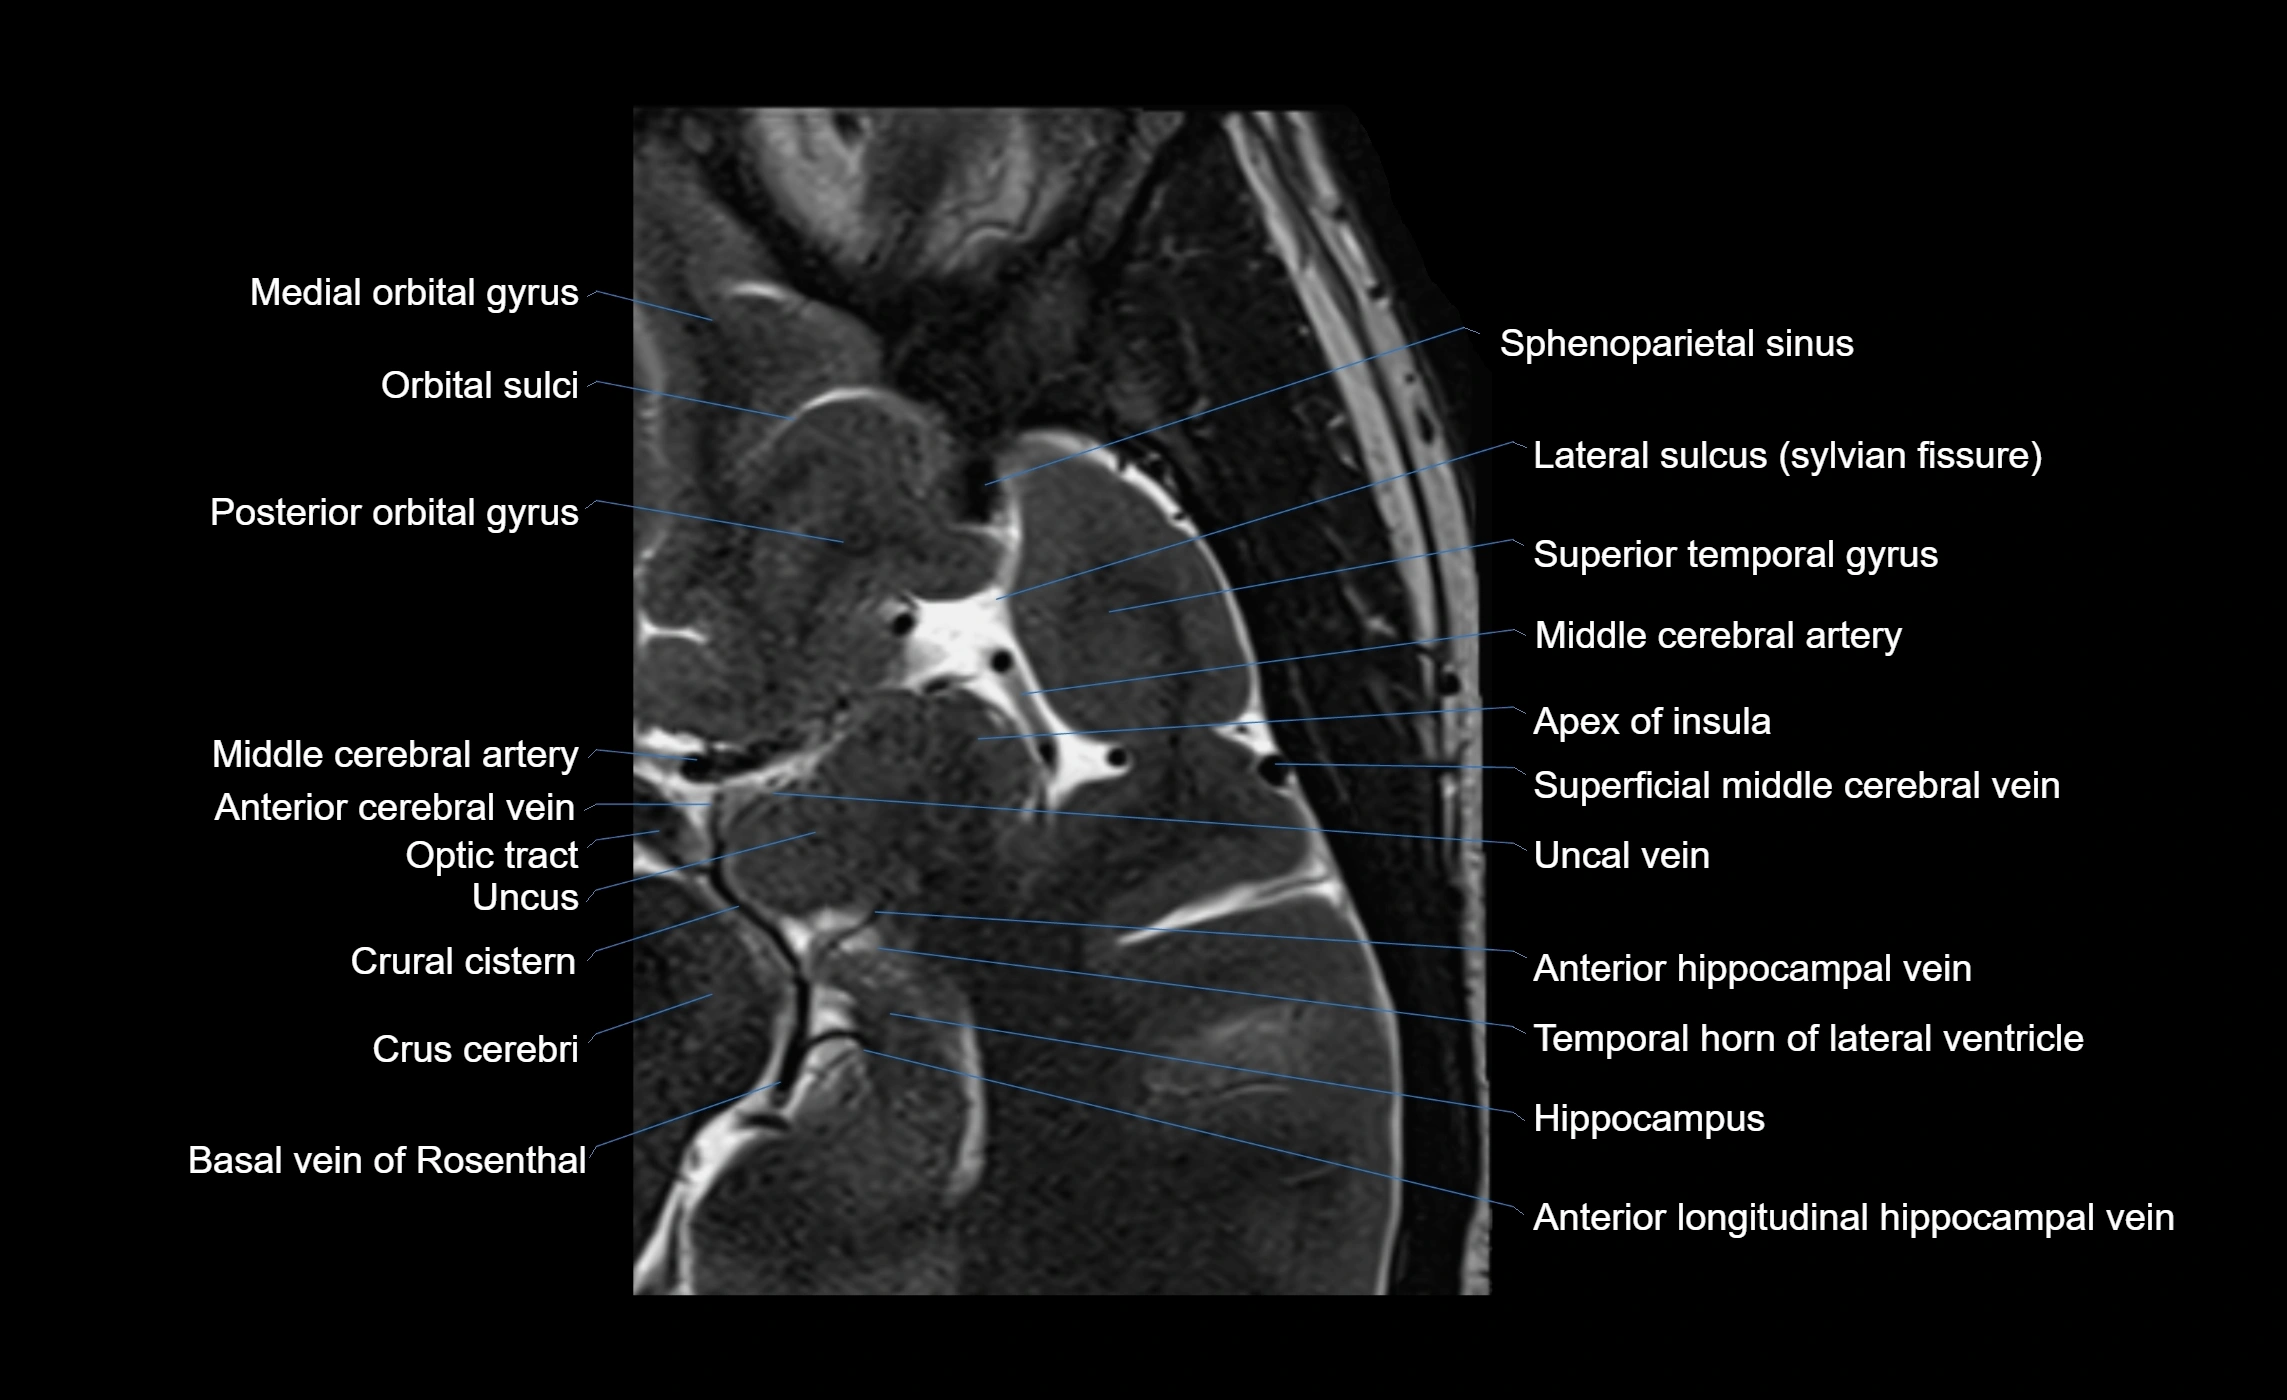

• T1-weighted imaging:

• The Sylvian fissure and its anterior ascending ramus appear as low-signal intensity (dark) CSF-filled clefts between the gyri.

• Clear demarcation between adjacent gray and white matter.

• T2-weighted imaging:

• The fissure, including the anterior ascending ramus, is hyperintense (bright) due to CSF signal.

• Better visualization of the separation between opercular and triangular parts of the inferior frontal gyrus.

• FLAIR imaging:

• The ramus is visualized as a linear dark space (suppressed CSF signal) between the surrounding cortex.

• Adjacent cortical and subcortical abnormalities (e.g., edema or gliosis) can be assessed relative to the ramus.